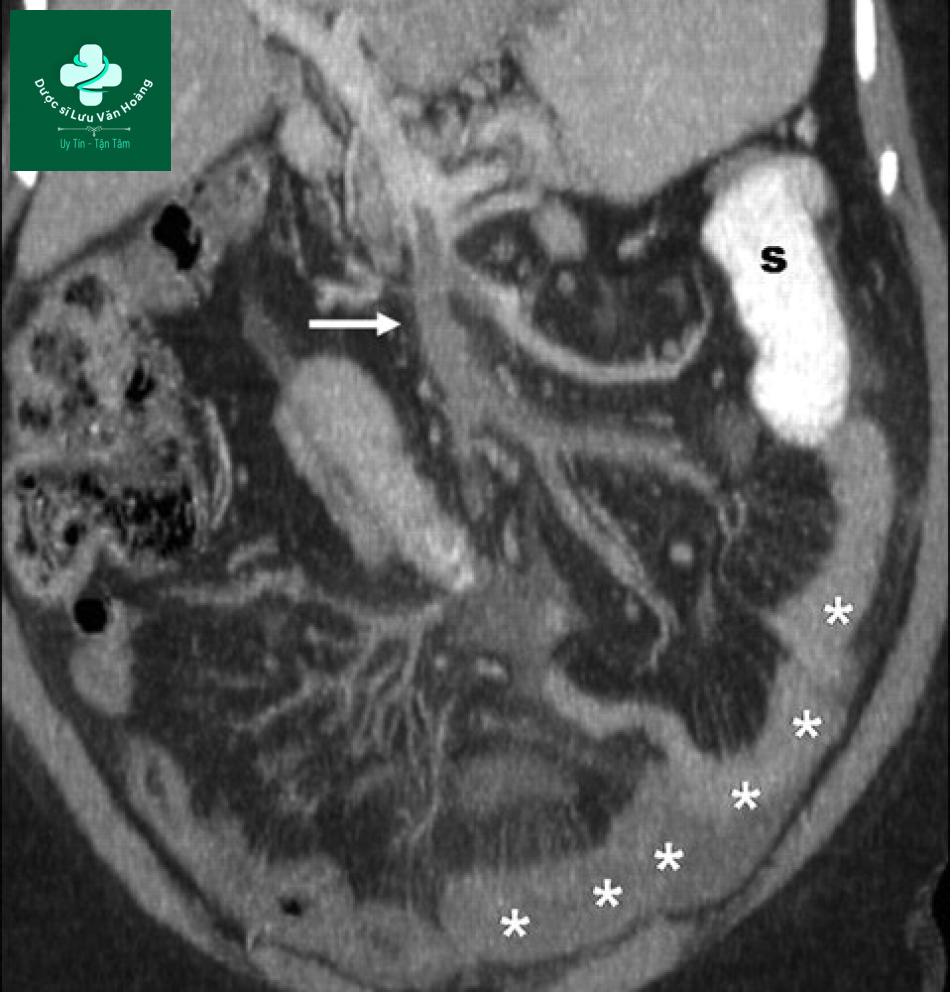

Tắc ruột sau huyết khối tĩnh mạch mạc treo tràng trên. Hình ảnh coronal cho thấy huyết khối trong tĩnh mạch (mũi tên) với dày thành các quai hồi tràng (dấu hoa thị) do phù dưới niêm mạc. S= giãn quai ruột non.